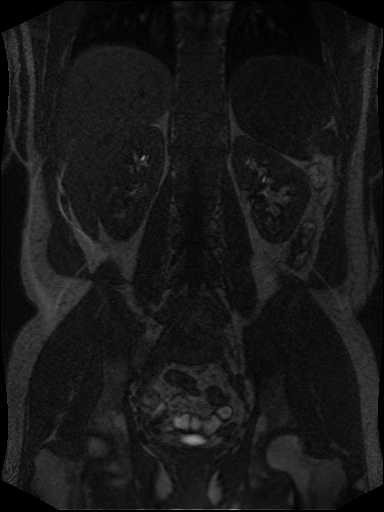

Example of MR Angiography with recording time before and after contrast agent infusion, respectively:

What do we see: Mainly kidneys, liver and and main supporting vessels aggregate contrast agent.